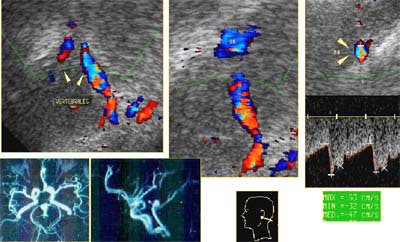

![]() |

| Valores normales de la velocidad del flujo sanguíneo de los vasos intracraneanos. Gráfico cortesía del Dr. Orlando Valls Pérez. |

"Las enfermedades cerebrovasculares se pueden detectar por el aumento o la disminución del flujo sanguíneo, la ausencia de flujo y los cambios espectrales", indicó Pérez. Al comparar los flujos de velocidad normal con los flujos medidos, también se puede evaluar la permeabilidad de los vasos. "Una vez que se conoce el flujo de sangre promedio de un vaso, se puede tener una muy buena idea de su fisiología", señaló.